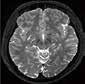

Ziel der Forschungen an der Universität Bordeaux war die hochaufgelöste und detailreiche Darstellung spezieller Hirnareale, wie des Hippocampus oder des Claustrum. Diese Regionen hatte Prof. Tourdias schon am 7T-System bei seinem Aufenthalt an der Stanford-Universität studiert. Nun war es mit der AiCE-Technologie möglich, vergleichbar aufgelöste Bilder auch bei 3T in akzeptabler Untersuchungszeit zu erzeugen (siehe Abb. 5 a und b).

Abb. 5 a + b: Hochaufgelöstes Bild des Hippocampus; 0,15 mm x 0,15 mm; 2 mm Schichtdicke; rechts mit AiCE-Rekonstruktion. Mit freundlicher Genehmigung des Unversitätsklinikums Bordeaux. Abb. 6 a + b: Hochaufgelöstes Bild des Knies; 0,15 mm x 0,15 mm (interpoliert); 1 mm Schichtdicke; rechts mit AiCE-Rekonstruktion.